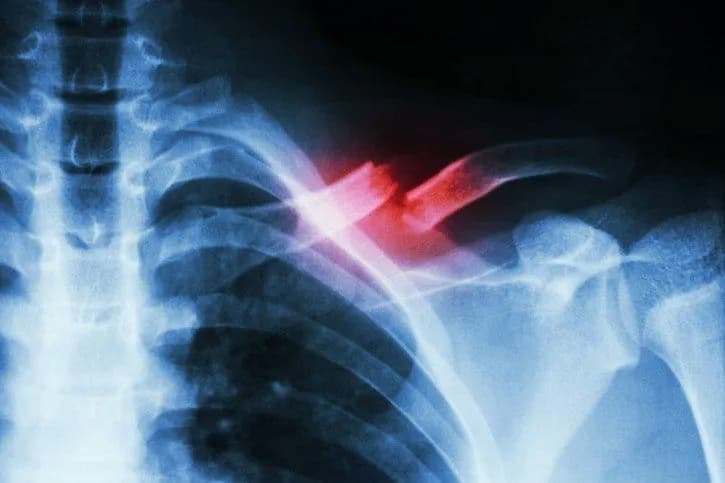

Istnieją różne typy złamań obojczyka, które mają różne implikacje dla procesu rehabilitacji. Złamania proste, w których kość nie przemieszcza się, wymagają mniej intensywnej rehabilitacji, co pozwala na szybszy powrót do zdrowia. Z kolei złamania z przemieszczeniem, które mogą wymagać operacji, często prowadzą do dłuższych okresów rehabilitacji i bardziej złożonych planów leczenia. W przypadku złamań z przemieszczeniem pacjenci mogą potrzebować dodatkowego czasu na regenerację i rehabilitację, co przekłada się na dłuższy czas powrotu do aktywności fizycznej.